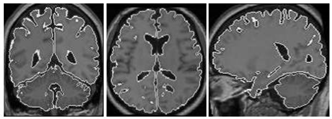

2.2. Segmentation of Brain Regions

2.2.1. Related-Work to the Segmentation of Brain Regions